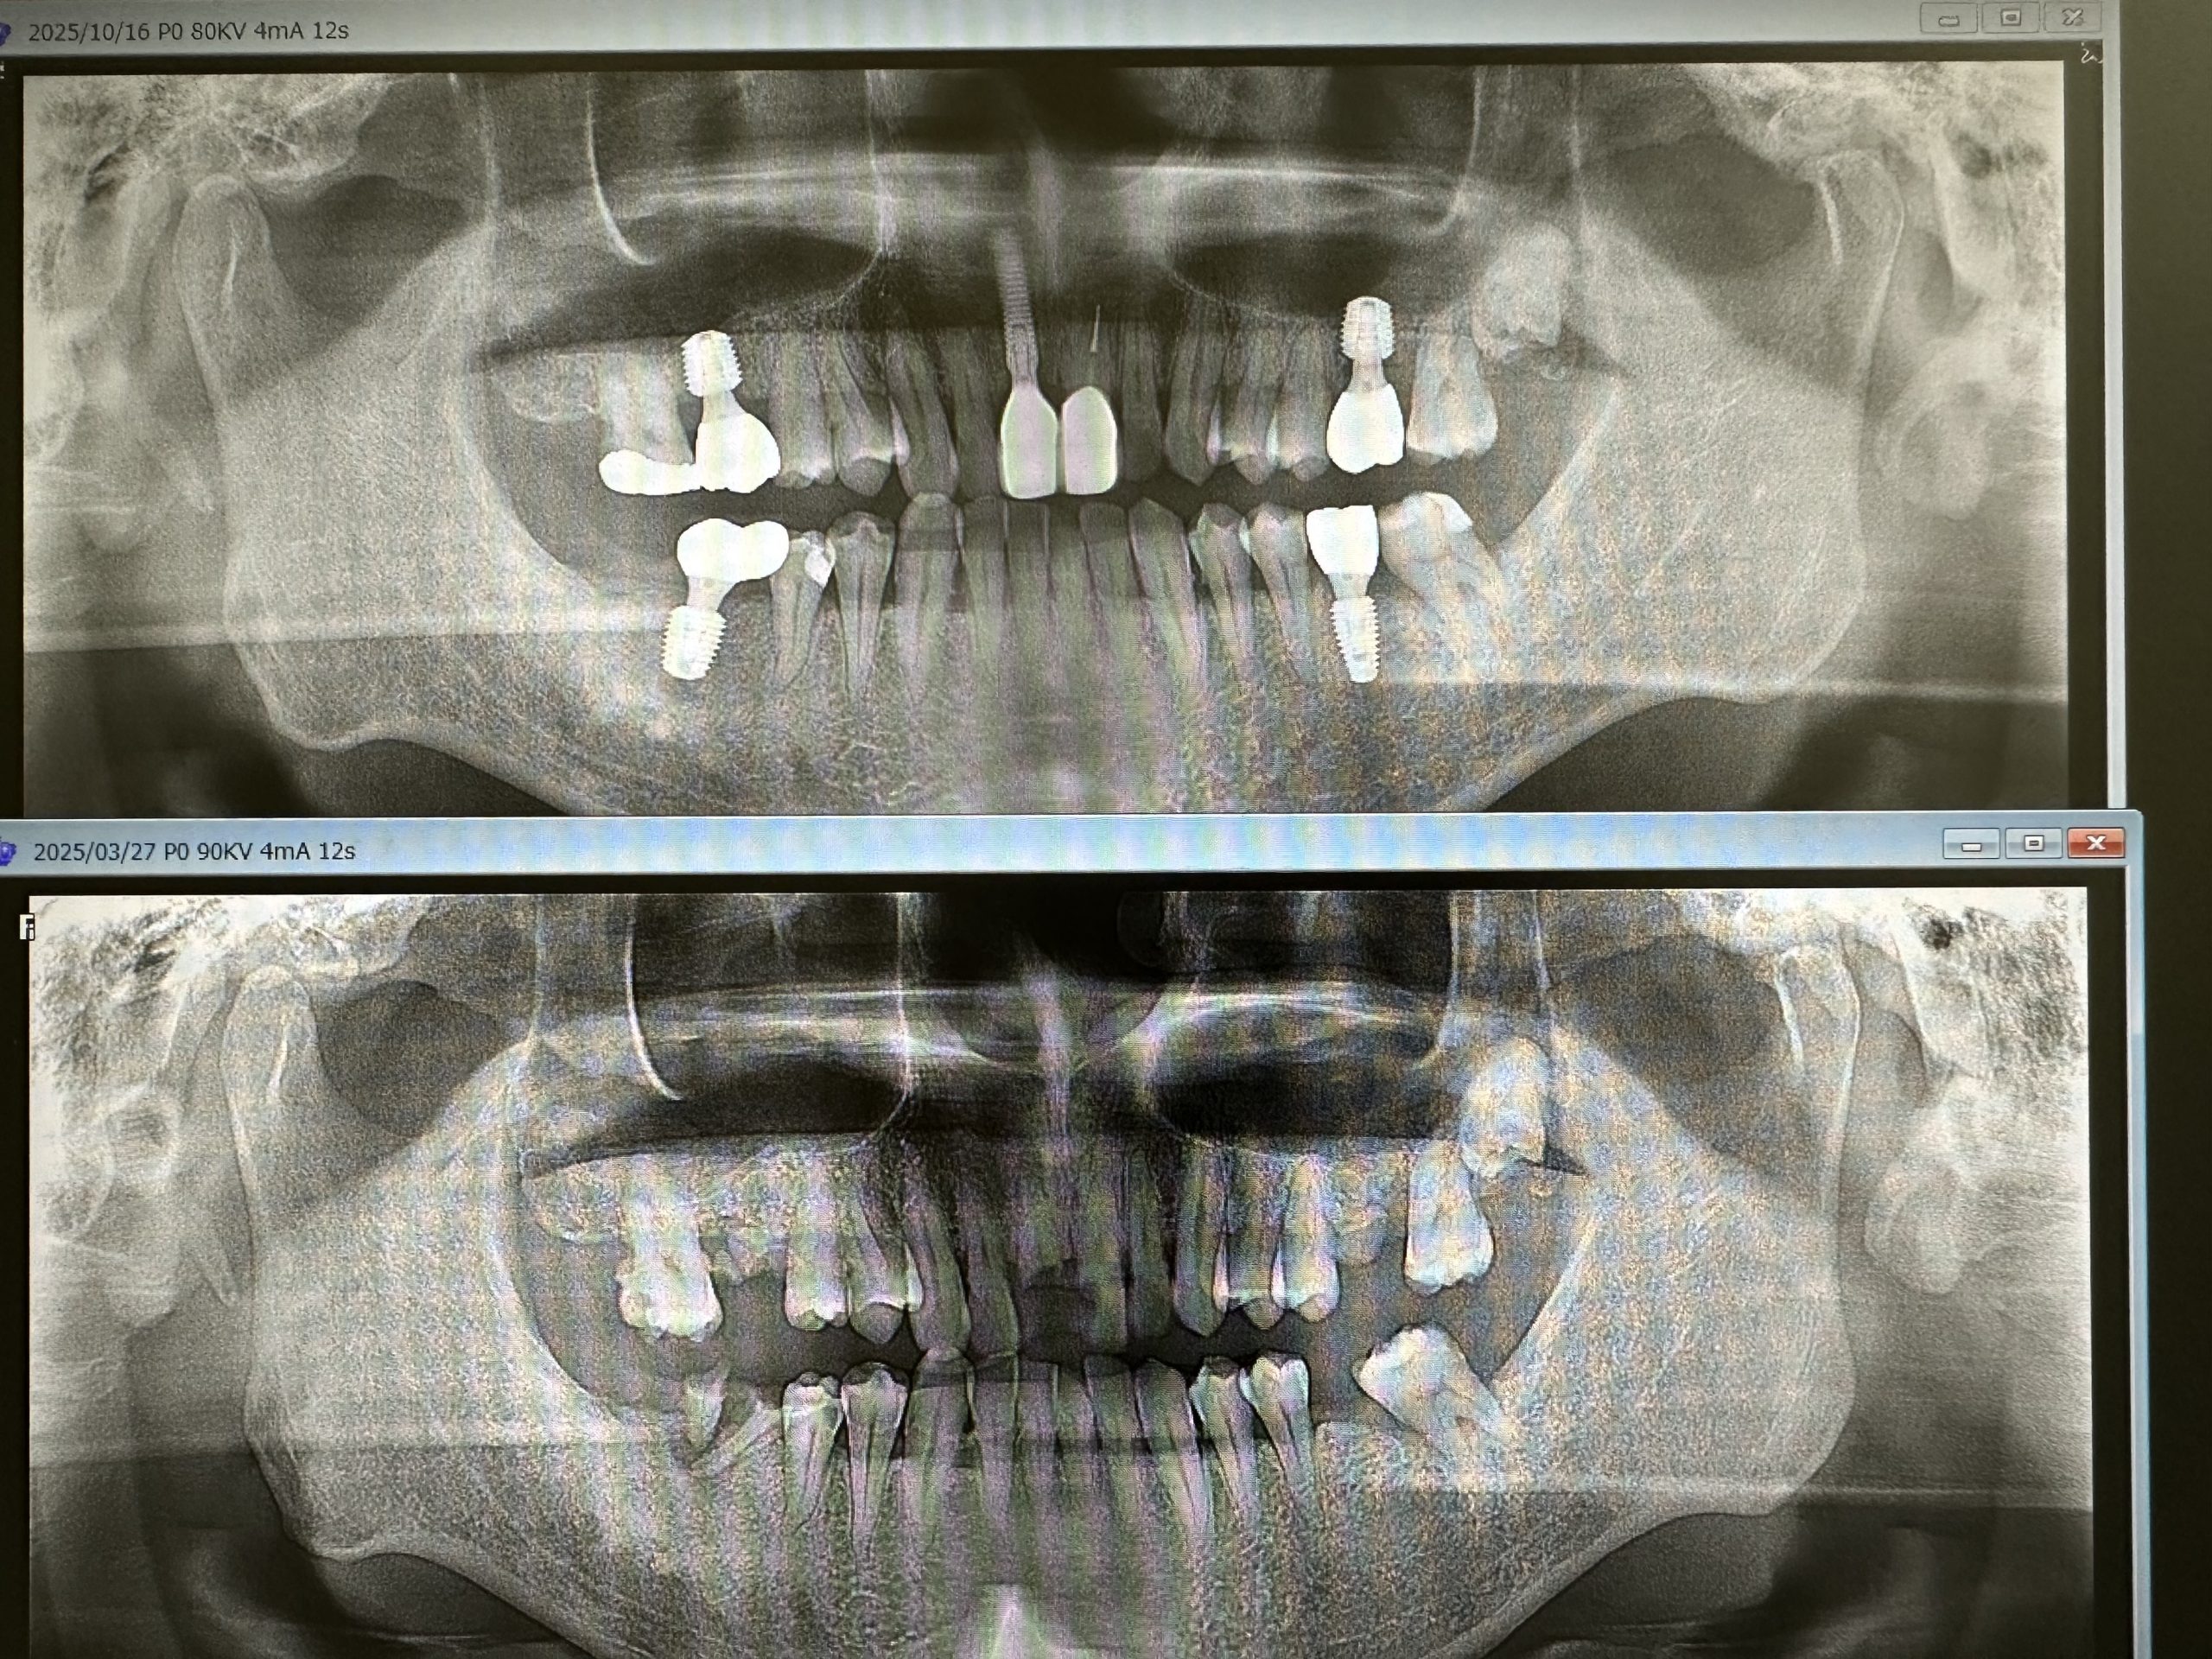

今日で終わり、定期検査に移行の方

インプラント5本、内ソケットリフト2本

今後の観察は、左上下6.7番隣接の骨が如何に増えるか!?動揺はだいぶ減少している💪